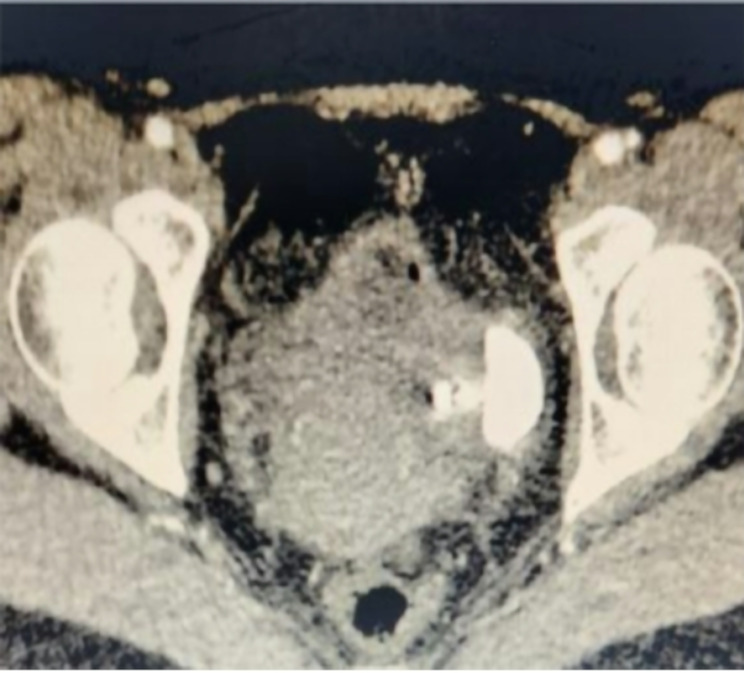

Vesicouterine fistula with vesical calculi secondary to IUD migration: a case report.